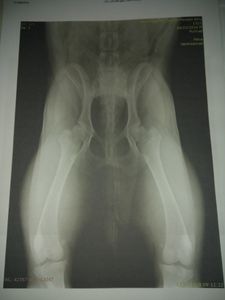

Em 2019, após não conseguir se levantar do chão, ele foi levado até um ortopedista veterinário que após analisar o rx deu o diagnóstico de Displasia Coxofemoral Bilateral que é uma doença genética e degenerativa, mas como estava em fase inicial foi prescrito dieta com especialista para ganho de massa muscular, caminhadas na praia e uso de suplemento manipulado para melhorar a sua qualidade de vida, longevidade, ganho de massa muscular e outros.

ESTE EXAME FOI REALIZADO EM 2019. INFELIZMENTE, POR CONTA DO PROBLEMA FINANCEIRO EU NÃO PUDE REALIZAR UM NOVO, MAS NAS IMAGENS POSTADAS ANEXAS VÊ-SE A PIORA DO QUADRO: